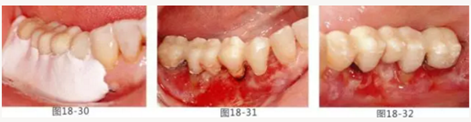

圖19-1 右下3,4,左下3,4,5殘存牙頰側面照。唇頰側沒有附著齦。

圖19-2 同部位的舌側面照。雖然有1mm左右角化牙齦,但是進行預測切開的話,會使角化牙齦完全消失。

圖19-3 左下3,4,5部位進行FGG(游離齦移植)去除牙周袋以及獲得附著齦。同時進行骨外科處理。相反側也進行同樣的處理。

圖19-4 將移植片固定于右下3,4左下3,4,5的舌側骨膜,并進行牙周袋去除以及獲得附著齦。

圖19-5,6 術后1個月唇舌側的愈合狀態(tài)。唇舌側都獲得了足夠附著齦。